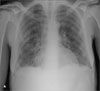

A 50-year-old woman presents to the emergency department with severe dizziness, weakness, and dyspnea of 1 week’s duration. Ten days earlier, an upper respiratory tract infection (URTI) was diagnosed; over-the-counter cough syrup and acetaminophen were prescribed. However, the patient’s condition has steadily deteriorated since then. In addition, her urine has darkened over the past few days.